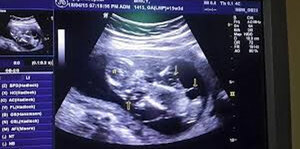

- Differentiate between different radiological modalities.

- Know the common terminology used in describing in different radiological modalities.